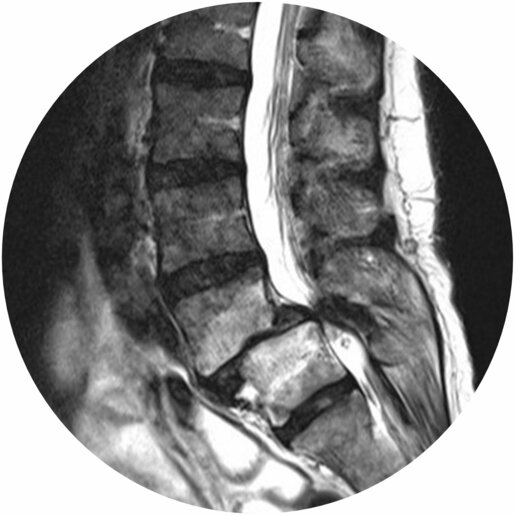

Bilder von links nach rechts.:

1. MRT einer Lendenwirbelsäule. Zu sehen ist ein Bandscheibenvorfall zwischen dem 5. Lenden- und dem 1. Kreuzbeinwirbelkörper.

2. MRT von der Schnittebene 1 (weiß gestrichelte Linie 1. Bild). Zu erkennen ist der nach hinten ausgetretene Bandscheibenvorfall (weiß gestrichelter Kreis), welcher nach hinten auf die Nervenwurzeln drückt (gelber Kreis).

3. MRT der Schnittebene 2 (rot gestrichelte Linie 1. Bild). Hier sieht man, wie viel Platz die Nervenwurzeln in der MItte ohne Bandscheibenvorfall haben (gelber Kreis).